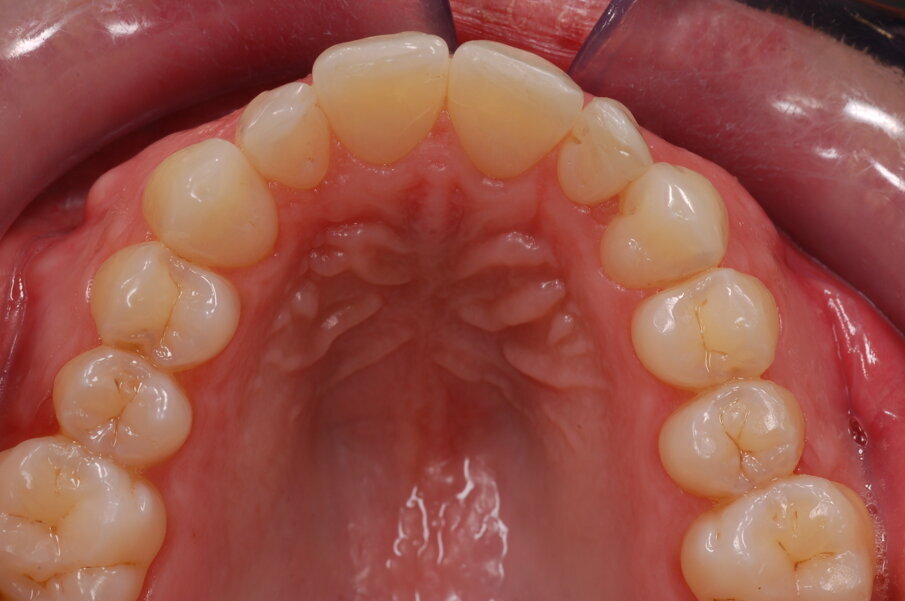

Diagnosi ed eziologia Un uomo sano di 39 anni si è presentato nel nostro studio ortodontico lamentando un aspetto dentale poco attraente e la paura della chirurgia ortognatica proposta da un altro ortodontista. Clinicamente, il profilo del paziente era rettilineo e la vista frontale non mostrava alcuna asimmetria facciale. L’esame funzionale non ha rivelato alcuna deviazione mandibolare o riduzione dei movimenti. Il paziente non aveva dolori articolari e non sono stati rilevati rumori articolari. Era presente una lieve occlusione molare bilaterale di Classe II, un morso aperto e un grave affollamento in entrambe le arcate. L’affollamento era particolarmente grave nell’arcata mandibolare, sebbene mancasse l’incisivo centrale mandibolare destro. Gli incisivi mascellari erano di piccole dimensioni, suggerendo una discrepanza dell’indice di Bolton se fossero stati presenti tutti e quattro gli incisivi mandibolari. Erano inoltre presenti un morso incrociato nella regione dell’incisivo laterale superiore sinistro e una grave rotazione distale del secondo premolare mandibolare sinistro (Figg. 1-8).

Figg. 1-8_Fotografie facciali e intraorali pre-trattamento.